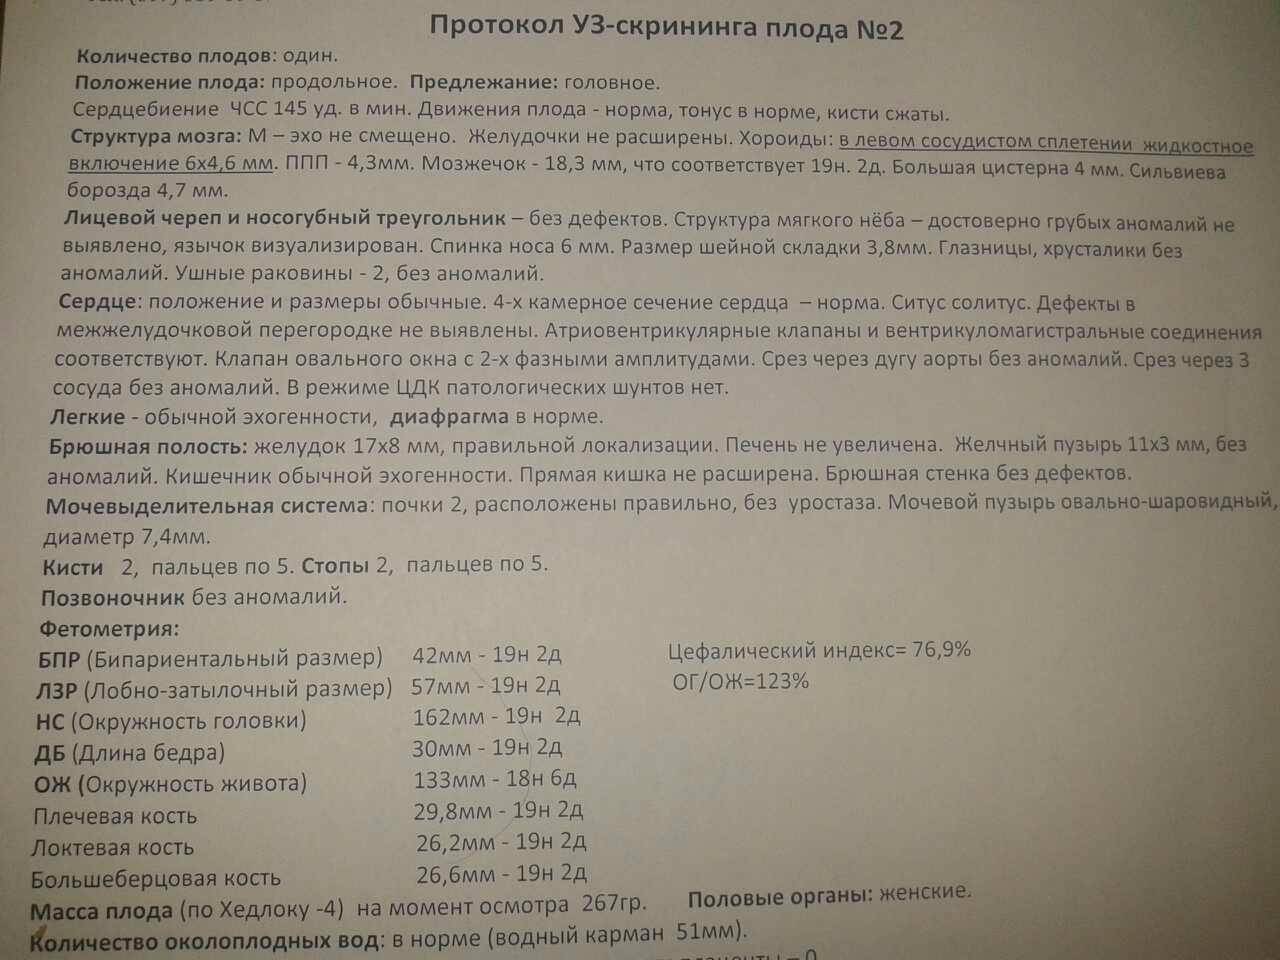

Нормы УЗИ 19-20 недель беременности